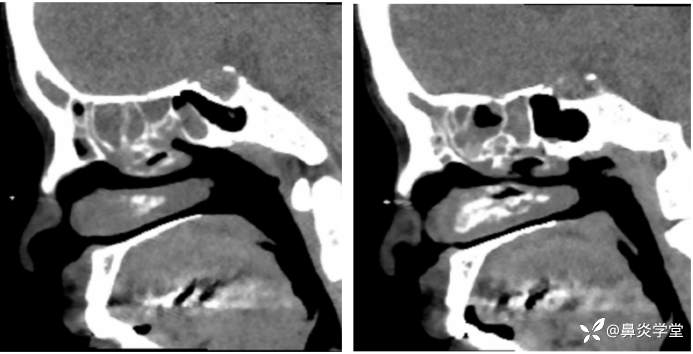

副鼻窦 CT:鼻息肉,鼻窦炎。两侧嗅裂炎性肉芽填充实变。

本例患者鼻内镜检查(见息肉)、鼻窦 CT(提示鼻窦炎),支持慢性鼻窦炎伴鼻息肉诊断。主要鉴别诊断如下[5]: